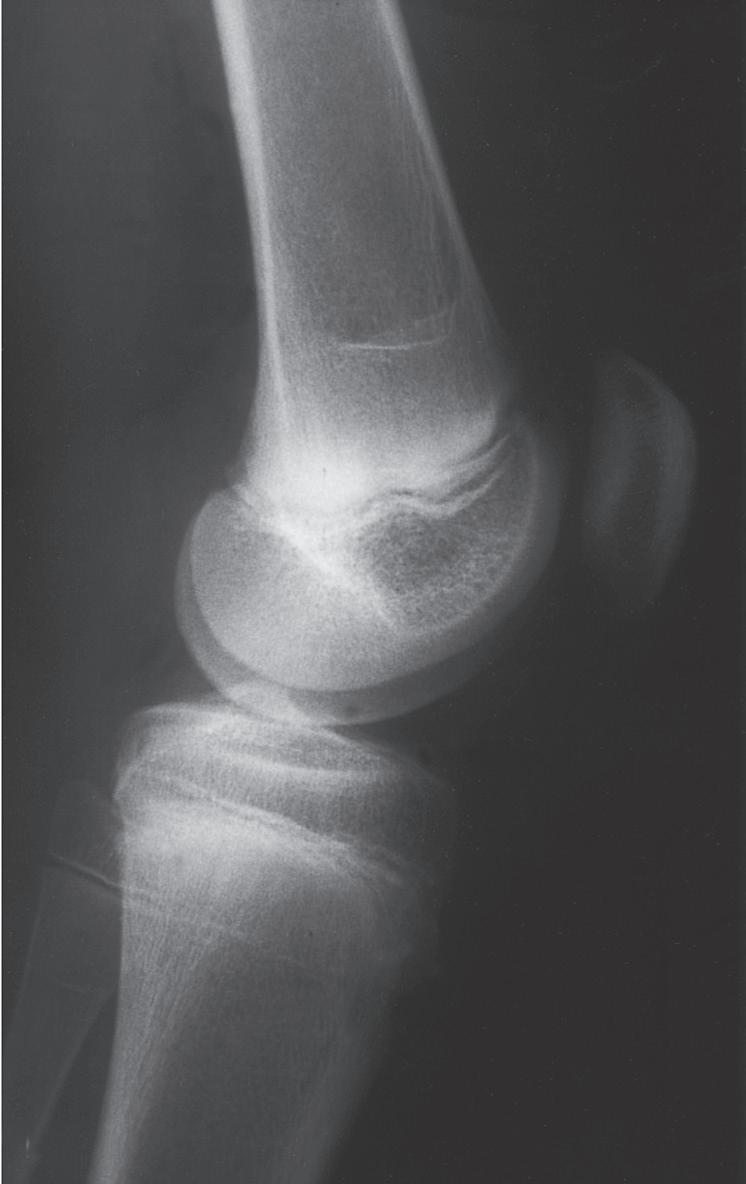

REMODELING AFTER A FRACTURE IN CHILDHOOD

The remodeling ability of bone in children may make reduction accuracy less important than it is in adults. Remodeling is a commonly used term in pediatric fracture care, implying that the child has the ability to straighten and correct residual deformity with growth. This capability depends not only on the mechanisms of bone remodeling described earlier during the remodeling phase of fracture healing (Wolff’s law) but also on reorientation of the physis by asymmetric growth after a fracture (Hueter-Volkmann law or Delpech’s law). Younger children have greater remodeling potential. The amount depends on the age of the child, location of the injury in the bone (proximity to the physis), degree of deformity, and whether the deformity is in the plane of motion of the adjacent joint.3,65,66 Clinical judgment and experience are required to guide decision-making regarding defining “acceptable” reductions, but obtaining the best reduction possible during initial treatment is advisable because it will lessen reliance on remodeling. Remodeling does not occur in displaced intraarticular fractures; thus reduction, usually by open methods, is needed. In children, remodeling is often relied on for the treatment of proximal humeral and distal radial injuries because these physes contribute greatly to the length of the respective segment, and the joints have wide ranges of motion. Remarkable remodeling has been documented in cases of these fractures (Fig. 1.4).

Remodeling may occur readily in the plane of a joint (Fig. 1.5), but it occurs far less readily, if at all, in children with rotational deformity or angular deformity not in the plane of the joint.14,65,66,69 Abraham67 studied the remodeling potential of immature monkeys and found that remodeling occurred at the growth plate and along the concavity of the shaft deformity, with minimal resorption on the convexity of the shaft. Diaphyseal remodeling and physeal reorientation with growth contributed similar amounts to the degree of remodeling. In femoral shaft fractures in children, 75% of the remodeling of angular deformities takes place in the physis, and 25% comes from appositional remodeling of the diaphysis.70 The physis adjacent to a fracture realigns itself with asymmetric growth to become perpendicular to the forces acting through the bone, and most authors believe this is the primary mechanism for remodeling.66